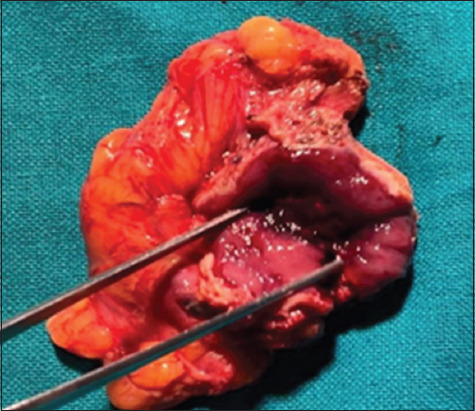

Case presentation: Presented here are three cases of incidental urinary bladder paraganglioma, all having hematuria as the primary symptom. During transurethral resection of bladder tumor, blood pressure fluctuated intensely with profuse bleeding, leading to the abandonment of the procedure. The patients were later diagnosed as having paraganglioma, and then, they were subjected to systemic evaluation and definitive treatment.